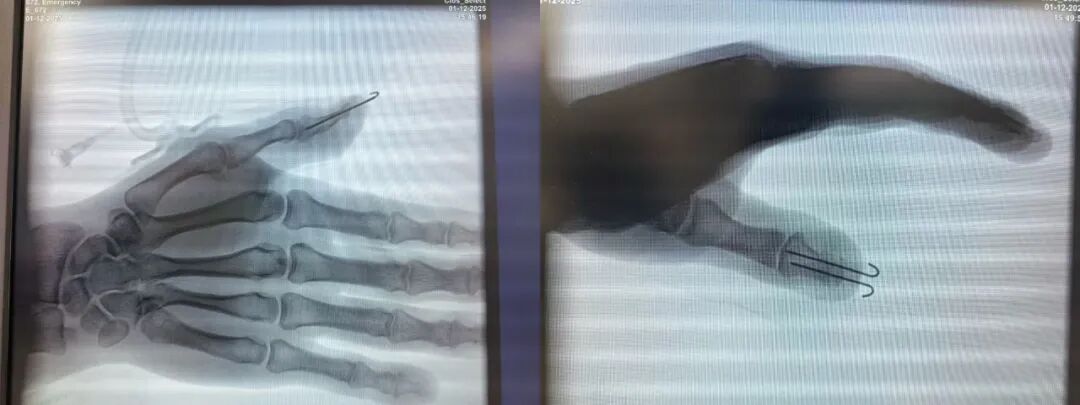

伤者是一名在生产一线作业的工人,其右手拇指在意外中被严重创伤,导致拇指不全离断,创面污染重,血管、神经、肌腱损伤情况不明。此类损伤的救治,远非简单“缝合”所能解决,关键在于术前与术中全面、精细的探查评估——必须清晰辨别每一根受损的血管、神经束,评估软组织活性,方能制定出真正个体化、最优化的修复方案。任何探查的疏漏,都可能导致术后血运障碍、感觉缺失或功能不全。

2. 解剖复位与稳固固定:在明确所有损伤结构后,团队将粉碎的骨折块进行解剖学精确复位,并使用两枚克氏针实施稳固的固定,为骨骼愈合和软组织修复提供了坚实的“内部支架”。